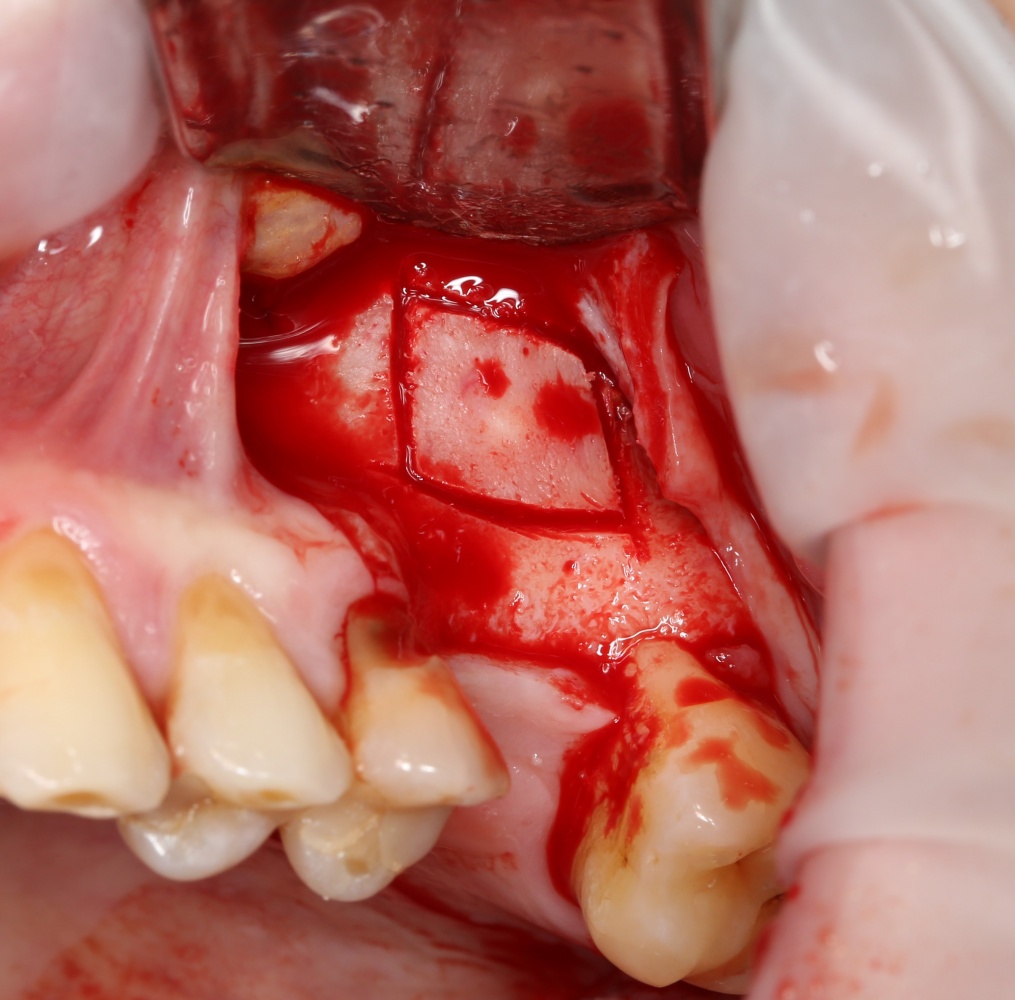

Возвращаемся к основной операционной области. Еще раз посмотрим на альвеолярный гребень, поофигеваем от его ширины и моих грандиозных планов:

На этом месте мне следует дать некоторые пояснения.

Если ты читал мои предыдущие публикации, посвященные остеопластике, то наверняка знаешь, что костное ложе перед фиксацией графта (любого графта) требует некоторой подготовки. В основном она заключается в полном или частичном удалении кортикального слоя и, применительно к АТККФ — адаптации не только блока под ложе, но и ложа под пересаживаемый костный блок. Подробности здесь>>

Ежу понятно, что к необходимости этих манипуляций мы пришли не сразу. А тогда был 2013 год… и у меня были мысли, что подготовка костного ложа нужна не всегда и не всем. Здесь я понадеялся на размер костного дефекта и большую площадь контакта между костным аутотрансплантатом и принимающим ложем. Конечно, сейчас я сделал бы немного по-другому.

Я зафиксировал костный блок практически без адаптации на несколько винтов. Обрати внимание, что винты находятся в зоне, где не планируется установка имплантатов. Фиксация должна быть надежной, поскольку мне еще предстояла подготовка лунок для имплантатов. Трех винтов для этого вполне достаточно.